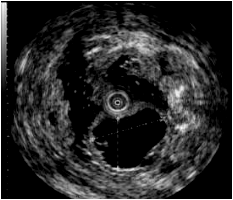

一、无痛胃肠镜检查技术我科在广西区内最早开展无痛胃肠镜检查技术,使病人可在无痛苦状态下完成整个检查和治疗过程。 二、激光放大染色内镜可清晰显示胃肠黏膜的腺管开口和微细血管等微细结构的变化,能比较准确地反映病变组织的病理学背景,区分增生性、腺瘤性和癌性病变,提高平坦和凹陷性早期癌的检出率,对消化道疾病的诊断及治疗具有重要的价值。 放大内镜下可见不规则微结构 BLI模式下可见不规则微血管三、早期消化道肿瘤ESD技术内镜下粘膜剥离术(ESD),具有超级微创、安全性高、住院时间短及费用低等优势。 直肠巨大绒毛状腺瘤 内镜下粘膜剥离过程 粘膜剥离术后创面 ...